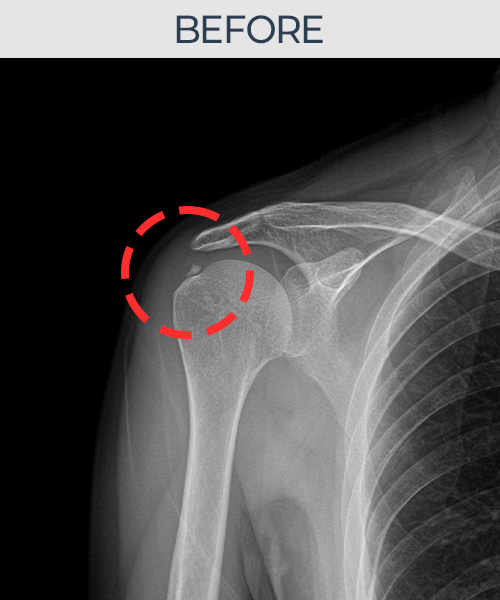

비수술 치료 전후사진

비수술로도 파열된 인대를

물리적으로 재건해 드립니다

플래티넘정형외과에서는 수술없이도 물리적으로

파열된 인대를 재건

하는것이 가능합니다.